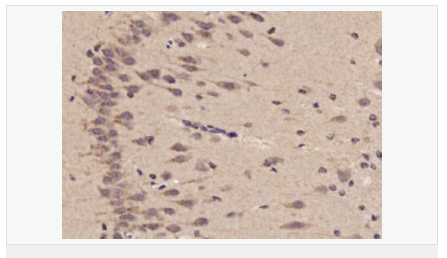

image.png